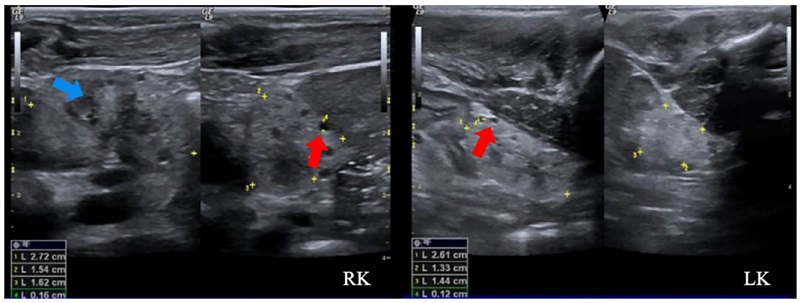

Se trató de un paciente de sexo masculino, producto de una unión consanguínea, que a los seis meses de vida presentó un episodio de pielonefritis. La ecografía renal mostró imágenes sugestivas de enfermedad poliquística renal autosómica recesiva, con múltiples imágenes quísticas bilaterales de ecogenicidad heterogénea y pérdida de la diferenciación corticomedular (figura 3). No presentaba lesiones hepáticas en la ecografía y la función hepática era normal.

A los cinco años de vida, una junta médica de genética clínica consideró que se trataba de una secuencia de obstrucción temprana de las vías urinarias (riñón multiquístico, diástasis de rectos abdominales y criptorquidia bilateral), con antecedentes familiares de consanguinidad parental, lo que sugiere una enfermedad poliquística renal de herencia autosómica recesiva. En un panel de secuenciación de nueva generación de los genes PKD1, PKD2 y PKHD1, no se encontraron variantes patogénicas en estos, por lo que se solicitó secuenciación de exoma en trío, actualmente en proceso.

Análisis. La enfermedad poliquística renal de herencia autosómica recesiva es una condición rara y de presentación usualmente grave en los primeros años de vida. Su incidencia se ha reportado como un caso por cada 26.500 recién nacidos vivos 18. Representa un espectro clínico que incluye la presencia de quistes que afectan los conductos colectores, así como nefromegalia, pérdida de la diferenciación corticomedular y fibrosis hepática; es causada principalmente por variantes bialélicas del gen de la fibrocistina (PKHD1), aunque también se han reportado variantes del gen DZIP1L (DAZ interacting protein 1-like) 19. Sin embargo, existe un gran número de síndromes con presentaciones similares (fenocopias), por lo cual se indica el diagnóstico molecular mediante secuenciación masiva paralela de múltiples genes. Se estima que en el 20 al 25 % de los pacientes no se encuentra la causa genética 20.